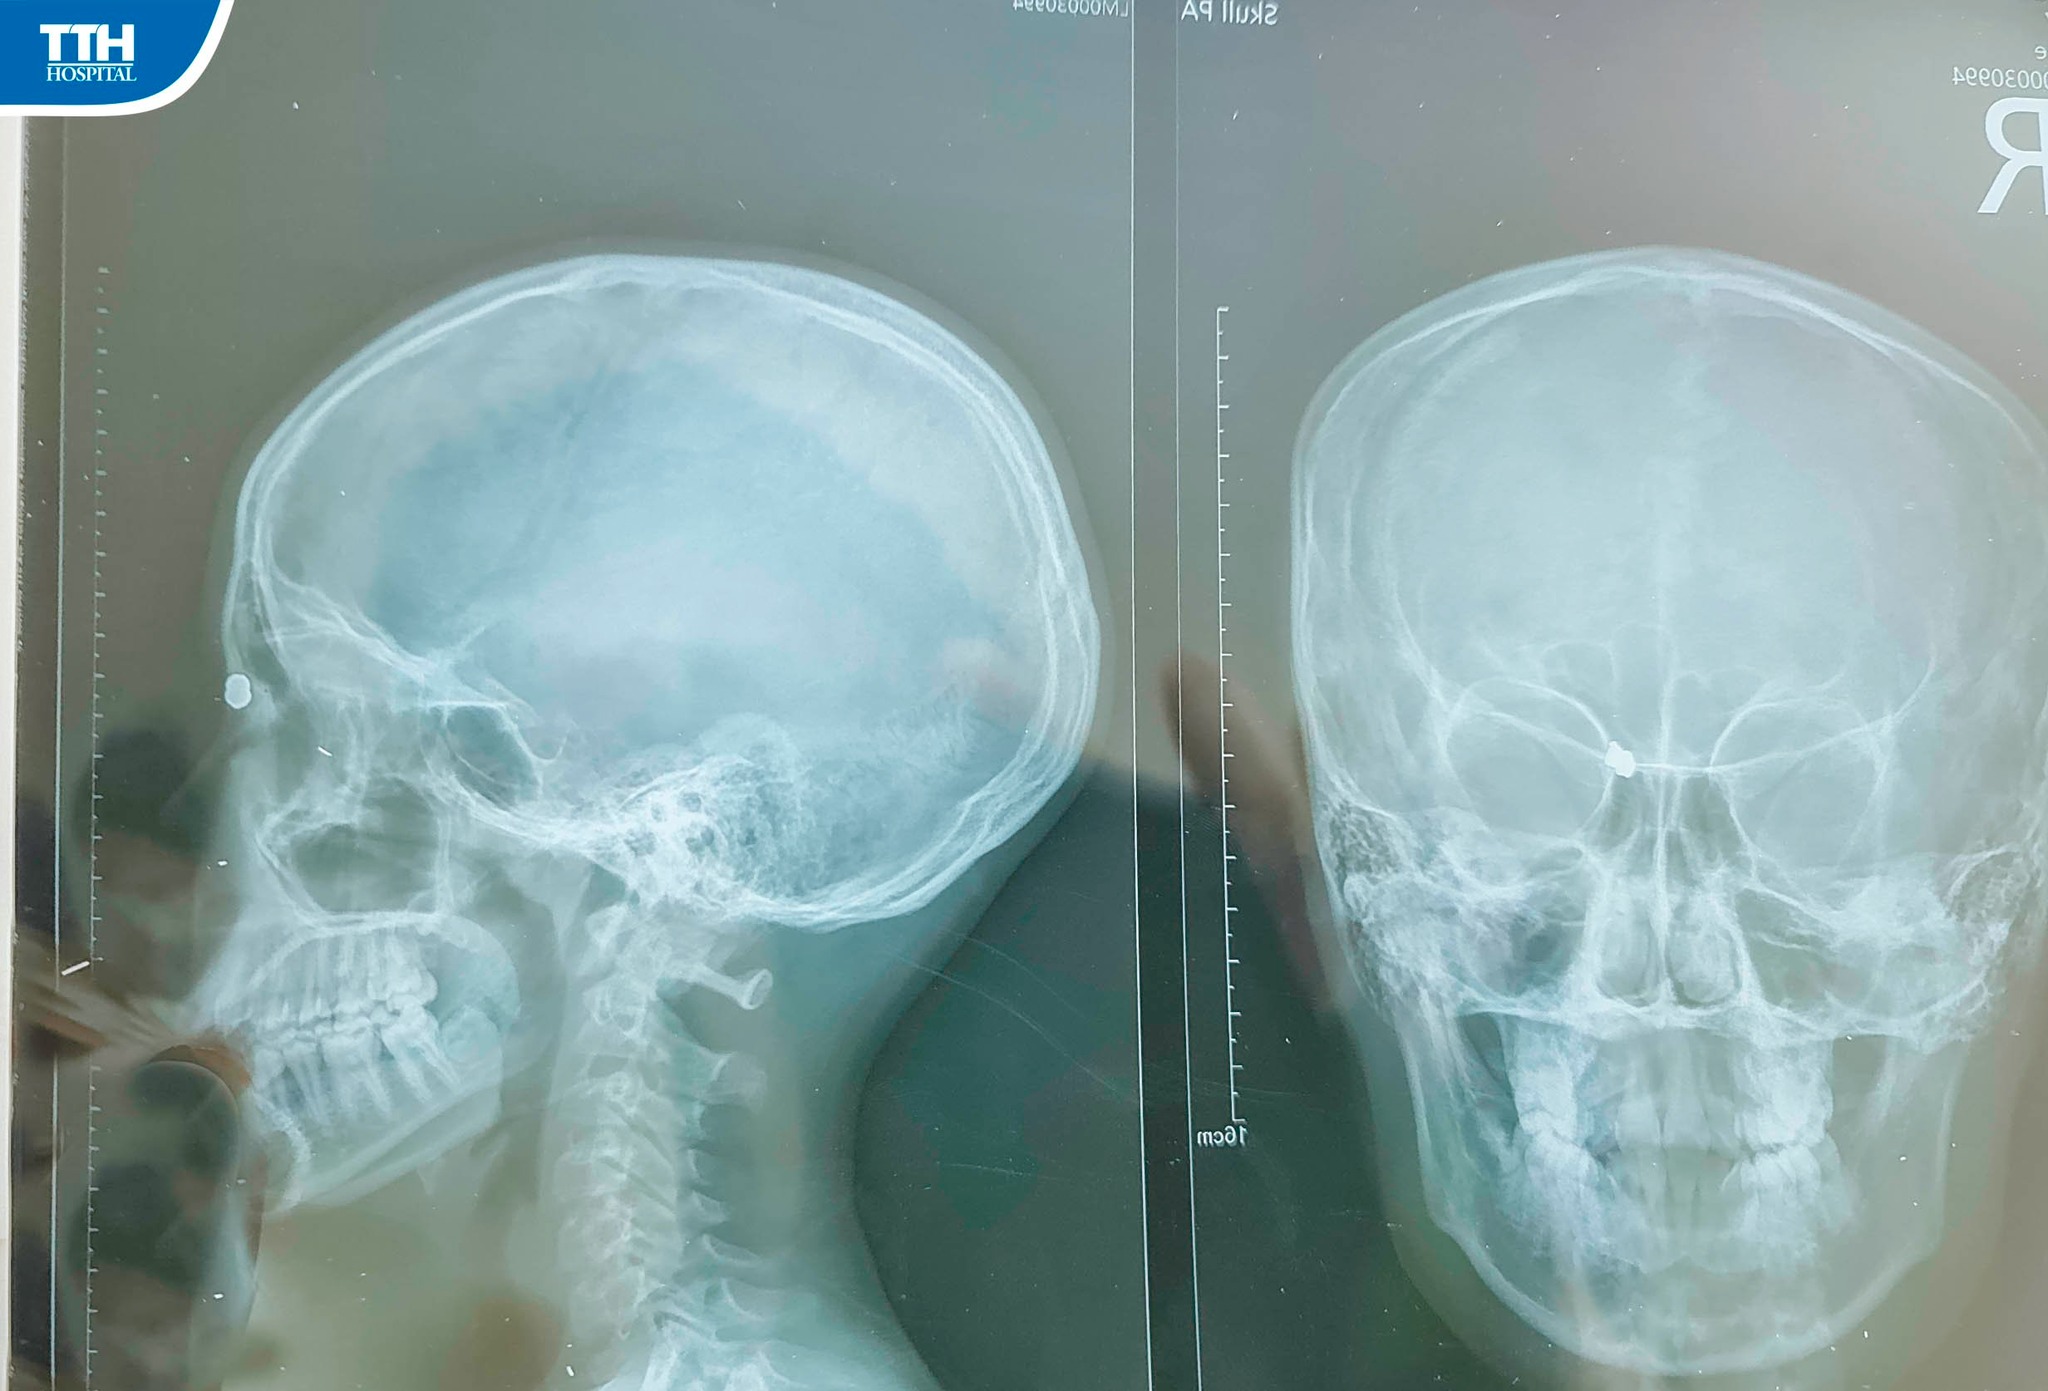

Vừa qua, Khoa Mắt – Bệnh viện Đa khoa TTH Hà Tĩnh, tiếp nhận bệnh nhi N.T.Đ (13 tuổi, Kỳ Anh, Hà Tĩnh). Bệnh nhi Đ nhập viện với triệu chứng đau trong hốc mắt, nửa đầu. Qua quá trình thăm khám, bác sĩ kết luận cháu Đ có một dị vật dạng kim khí nằm trong hốc mắt trái. Ngay sau đó, bác sĩ đã chỉ định tiến hành phẫu thuật để lấy dị vật.

Mẹ của cháu Đ cho biết: ''Cách đây 4 năm về trước, trong 1 lần đi chơi cùng bố mẹ, cháu Đ không may bị một thanh niên cùng địa phương sử dụng súng tự chế bắn trúng vào hốc mắt trái. Vì vết thương dần hồi phục và cháu Đ không có biểu hiện đau nhức nên không đưa tới cơ sở y tế để thăm khám. Gần đây, cháu Đ có biểu hiện đau trong hốc mắt trái và nửa đầu nên gia đình đã quyết định đưa cháu đến Bệnh viện Đa khoa TTH Hà Tĩnh khám để tìm ra nguyên nhân thì phát hiện ra dị vật vẫn còn nằm trong hốc mắt''.

Theo BS. Nguyễn Đức Anh, khoa Mắt – Bệnh viện Đa khoa TTH Hà Tĩnh: “Trường hợp dị vật nằm trong hốc mắt trái của cháu Đ là trường hợp hiếm gặp, sau khi phát hiện, phương án tối ưu đưa ra là phải phẫu thuật lấy dị vật ra. Đặc biệt, với trường hợp của cháu Đ, dị vật đạn chì đã nằm trong hốc mắt 4 năm, rất dễ gây biến chứng, ngộ độc chì”.